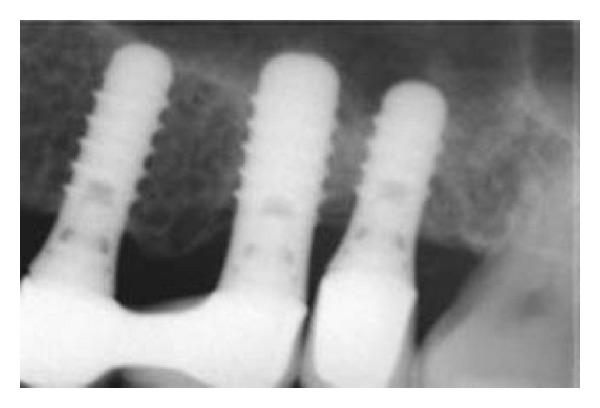

This case report discusses osteotome sinus floor elevation (OSFE) and immediate placement in 2 stages in severely resorbed alveolar bone height in which multiple implant placement is not otherwise feasible due to a lack of initial stability. The first implant placed using OSFE without bone grafting prepares the adjacent resorbed sites for further implant placement in the sinus areas, which allows for better initial stability and early functional loading. This process avoids the conventional extensive lateral approach for sinus lifting and bone grafting procedures even in extremely resorbed alveolar bone.

本病例报告讨论了骨凿上颌窦底提升术(OSFE)以及在严重吸收的牙槽骨高度中分两阶段即刻种植的情况,在这种情况下,由于缺乏初始稳定性,否则无法进行多颗种植体植入。使用OSFE且不进行骨移植植入的第一颗种植体为在窦区进一步植入种植体准备相邻的吸收部位,这允许更好的初始稳定性和早期功能负荷。即使在牙槽骨极度吸收的情况下,该过程也避免了传统的广泛外侧入路进行上颌窦提升和骨移植手术。